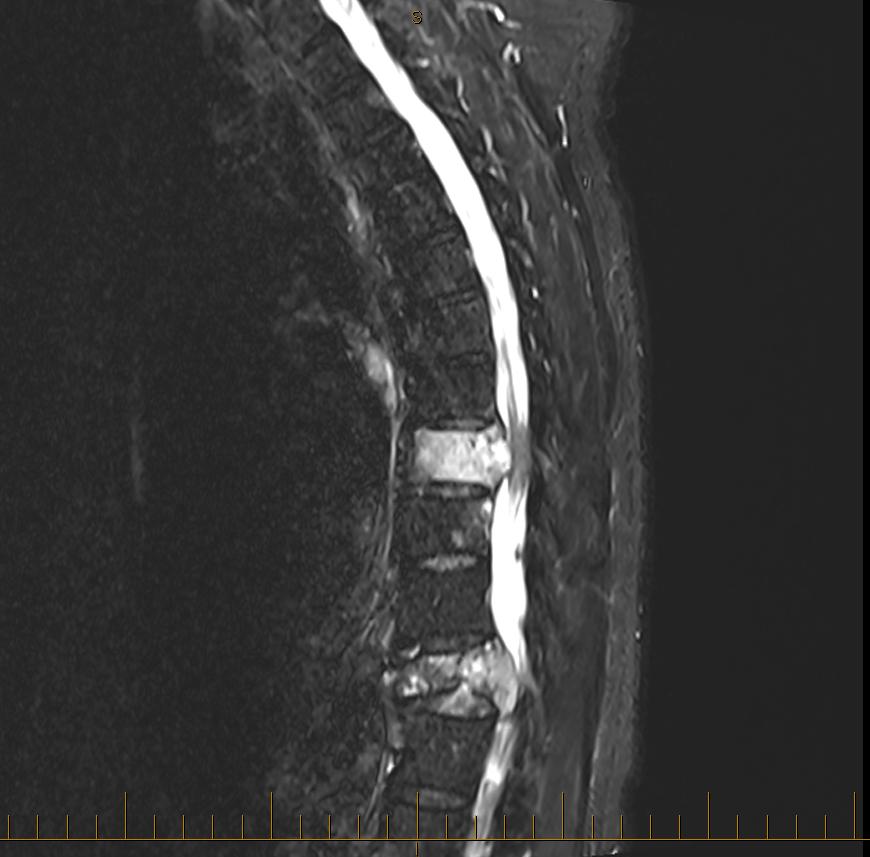

The miracle drug ENHERTU is now stuck in New Zealand customs and the tumour keeps pushing against my spinal cord.

I have posted this image to show the tumours on my spine that are trying to make me a paraplegic. Normal is a lovely long white line.